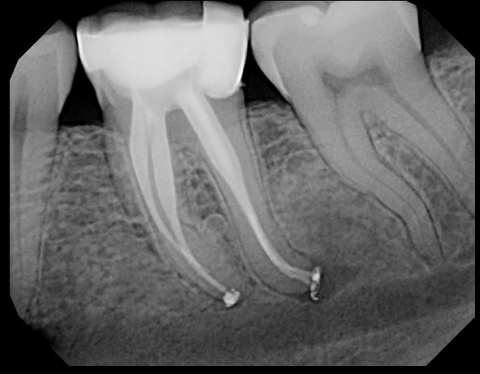

- And the final solution is of course to have endodontic or root canal treatment performed on the tooth. Granted, this is not inexpensive but the only other alternative is to have the tooth removed. Sadly this is often the realistic choice for many people but it’s a slippery slope. Fewer teeth only means more stress for the remaining teeth. Canada is a bit of an anomaly amongst the nations with universal health care. Drugs and Dentistry are not covered by our version of less than universal health care.

So even if you conscientiously brush and floss your teeth daily, watch your diet and live a healthy life – you too could experience a toothache later in life. Antibiotics will not help you. This type of first world toothache is not caused by advanced tooth decay introducing a bacterial infection into your jaw but is an inflammation of the nerve fibers residing in each living tooth as it begins to degenerate and die. This is brought on by the accumulated stresses of cracks, fractures, chips, load, old fillings and wear. The tooth begins by becoming hypersensitive to normal stimuli and develops to outright pain.